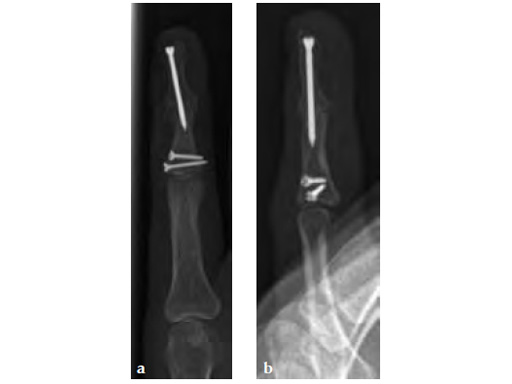

A 22-year-old female with previous complex fractures of the base and head of the middle phalynx (proximal screws are from the previous fracture fixation) presented with a residual painful, deformed, and stiff DIP J. Joint arthrodesis planned.

Case provided by Robert Farnell, Leeds, UK

The arthrodesis was performed using the longest available screw. Note that despite this it has only just crossed the arthrodesis site (see Fg 2a-b)